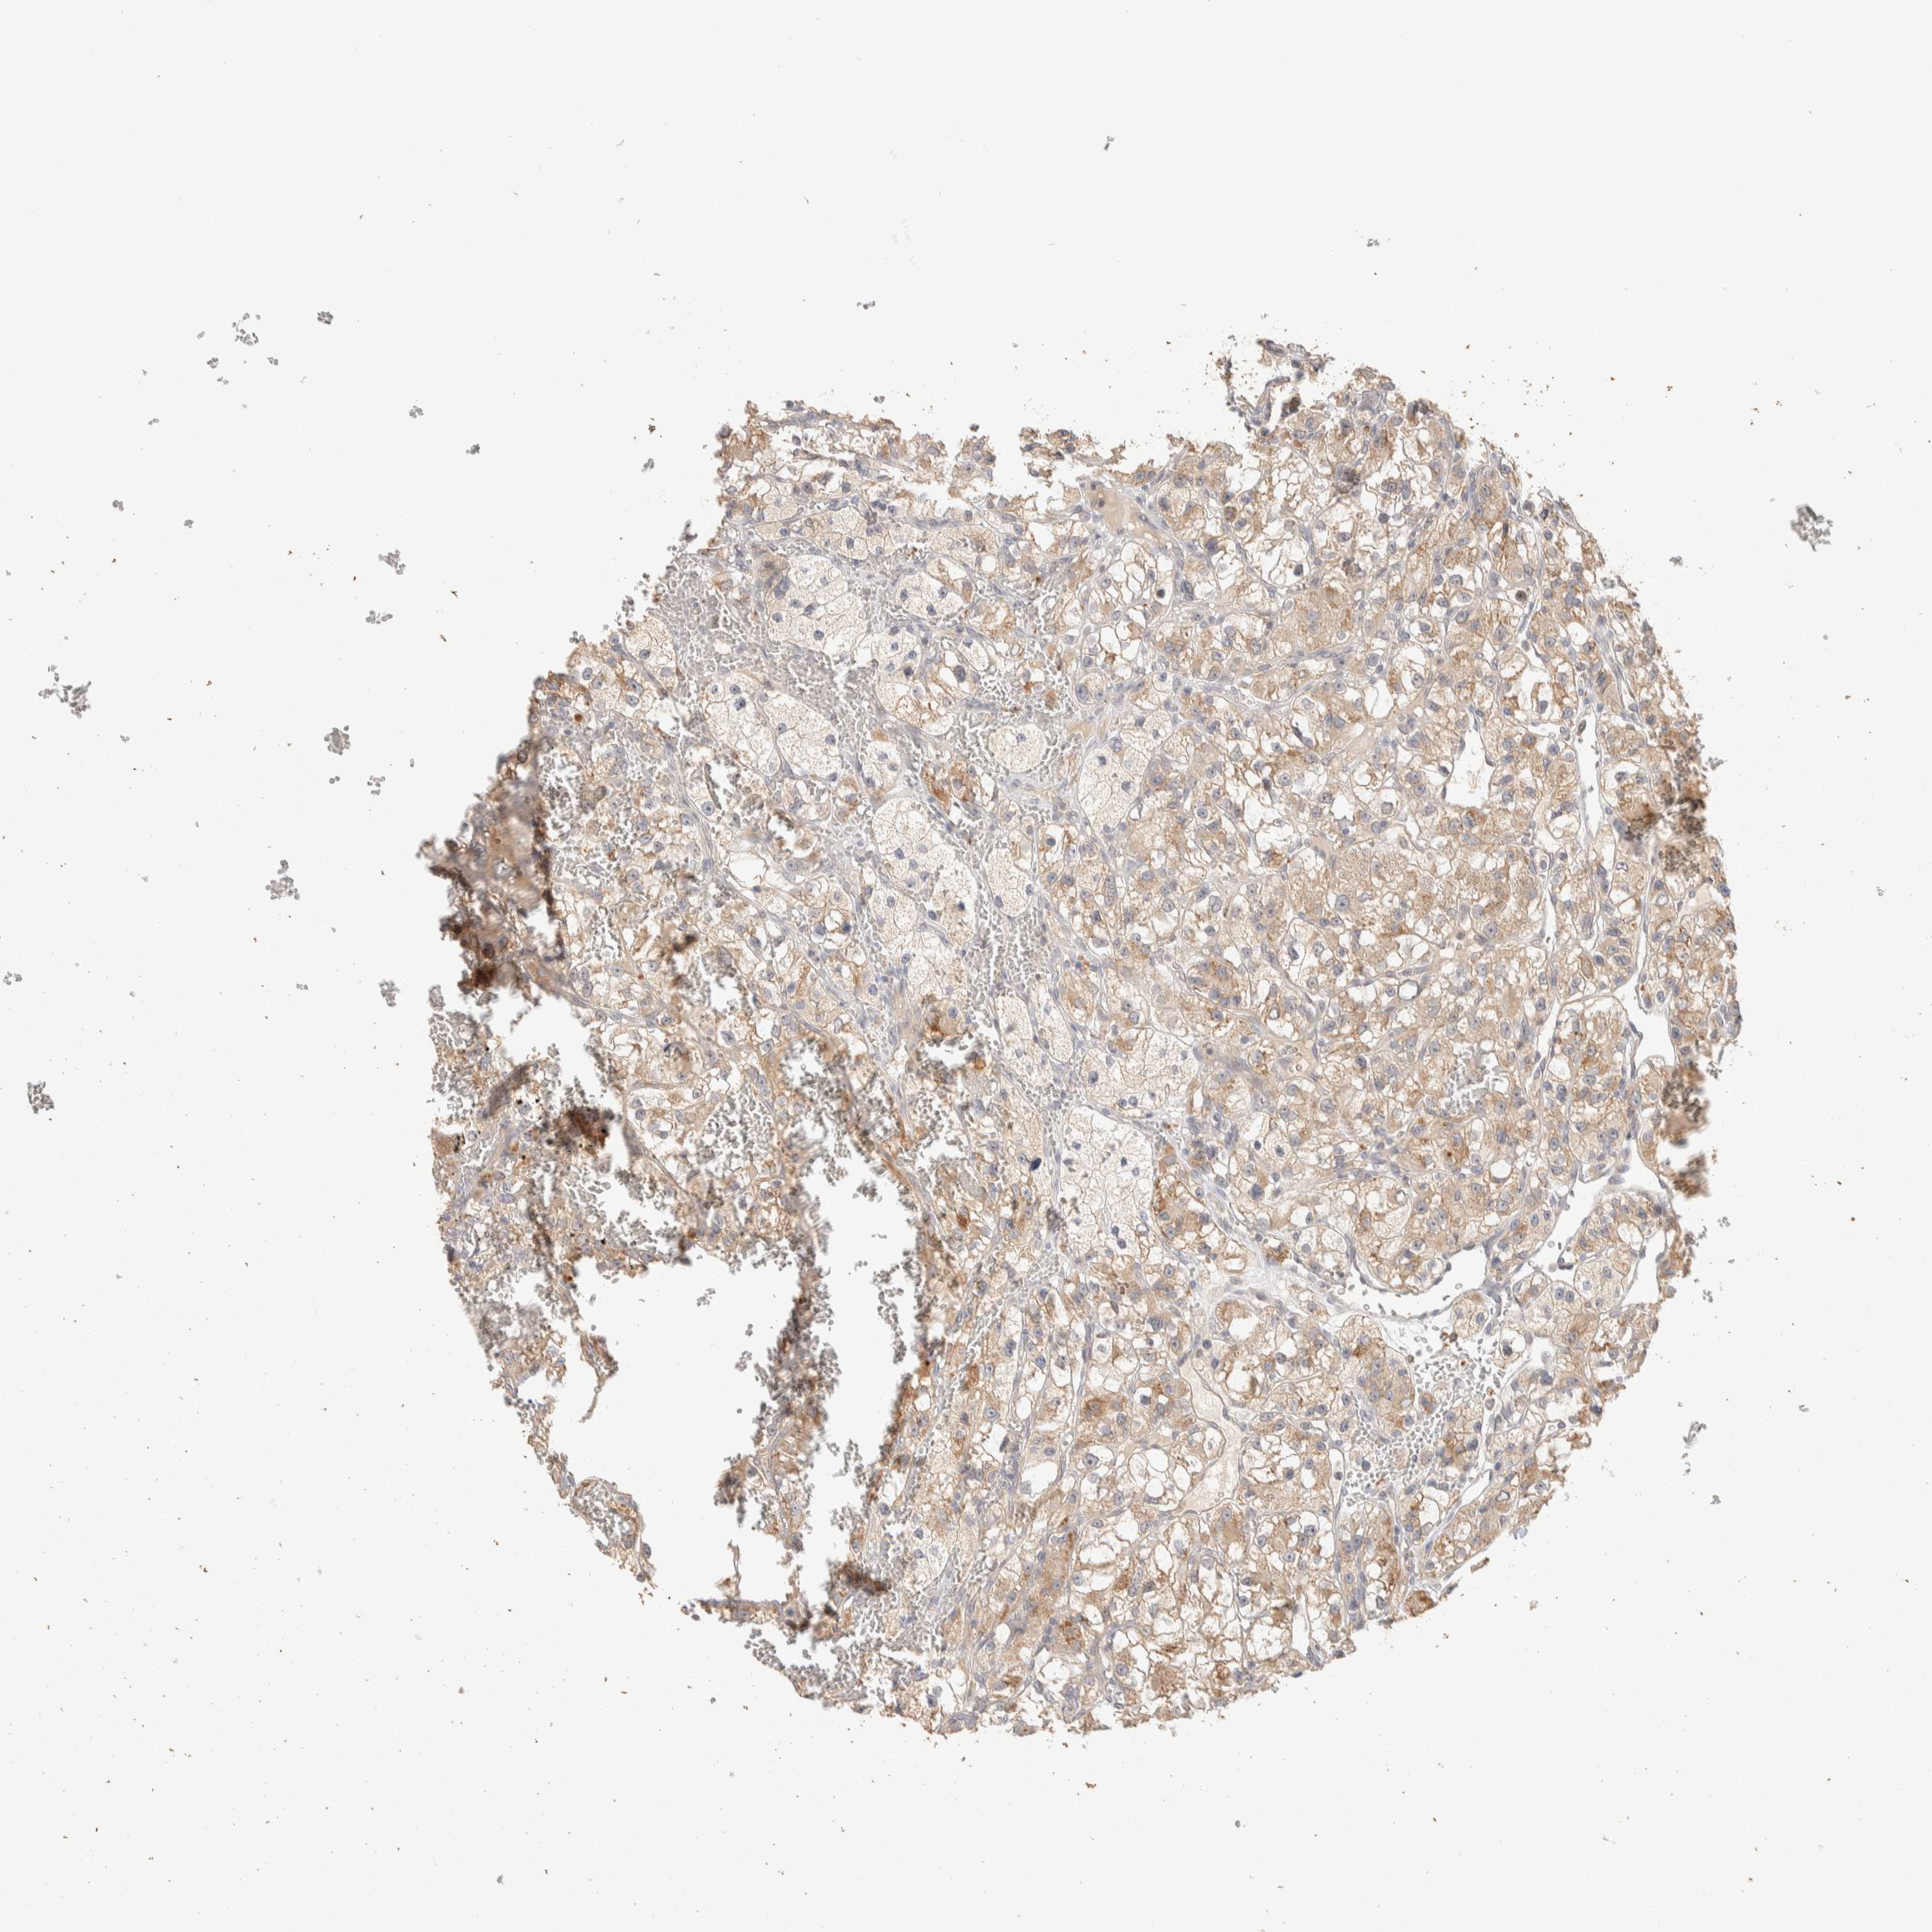

KIDNEY RENAL CLEAR CELL CARCINOMA (TCGA) - Interactive survival scatter ploti

The Survival Scatter plot shows the clinical status (i.e. dead or alive) for all individuals in the patient cohort, based on the same data that underlies the corresponding Kaplan-Meier plots. Patients that are alive at last time for follow-up are shown in blue and patients who have died during the study are shown in red.

The x-axis shows the expression levels (FPKM) of the investigated gene in the tumor tissue at the time of diagnosis. The y-axis shows the follow-up time after diagnosis (years). Both axes are complimented with kernel density curves demonstrating the data density over the axes. The top density plot shows the expression levels (FPKM) distribution among dead (red) and alive patients (blue). The right density plot shows the data density of the survived years of dead patients with high and low expression levels respectively, stratified using the cutoff indicated by the vertical dashed line through the Survival Scatter plot. This cutoff is automatically defined based on the FPKM cutoff that minimizes the p-score. The cutoff can be changed by dragging the vertical line or by entering a cutoff value in the square labeled "Current cut-off".

Under the Survival Scatter plot the p-score landscape (black curve; left axis) is shown together with dead median separation (red curve; right axis). Dead median separation is the difference in median mRNA expression between patients who have died with high and low expression, respectively. It is calculated as follows: median FPKM expression of dead patients with high expression - median FPKM expression of dead patients with low expression. This is intended to aid the user in visually exploring custom cutoffs and the associated p-scores and dead median separation.

Individual patient data is displayed and can be filtered by clicking on one or more of the category buttons on the top of the page. Categories describing expression level and patient information include: high, low, alive, dead, female, male and tumor stages. The scale of the x-axis can be toggled between linear and log-scale by clicking on the "x log" button. Mouse-over function shows TCGA ID, patient information and mRNA expression (FPKM) for each patient.

& Survival analysisi

Kaplan-Meier plots summarize results from analysis of correlation between mRNA expression level and patient survival. Patients were divided based on level of expression into one of the two groups "low" (under cut off) or "high" (over cut off). X-axis shows time for survival (years) and y-axis shows the probability of survival, where 1.0 corresponds to 100 percent.

ITPA is not prognostic in Kidney Renal Clear Cell Carcinoma (TCGA)

Best expression cut offi

Based on the FPKM value of each gene, patients were classified into two groups and association between prognosis (survival) and gene expression (FPKM) was examined. The best expression cut-off refers the FPKM value that yields maximal difference with regard to survival between the two groups at the lowest log-rank P-value. Best expression cut-off was selected based on survival analysis .

When clicking on this number, the vertical dashed line indicating cut-off, the interactive survival plot, and the Kaplan-Meier curve will be adjusted to show results based on the best expression cut-off.

: 50.97

P scorei

Log-rank P value for Kaplan-Meier plot showing results from analysis of correlation between mRNA expression level and patient survival.

N/A

5-year survival highi

5-year survival for patients with higher expression than the expression cutoff.

For melanoma and glioma, 3-year survival is shown.

5-year survival lowi

5-year survival for patients with lower expression than the expression cutoff.

TCGA RNA samplesi

RNA-seq data is reported as average FPKM (number Fragments Per Kilobase of exon per Million reads), generated by the The Cancer Genome Atlas (TCGA) .

Normal distribution across the dataset is visualized with box plots, shown as median and 25th and 75th percentiles. Points are displayed as outliers if they are above or below 1.5 times the interquartile range. FPKM values of the individual samples are presented next to the box plot.

Average pTPM 45.3

Number of samples 521